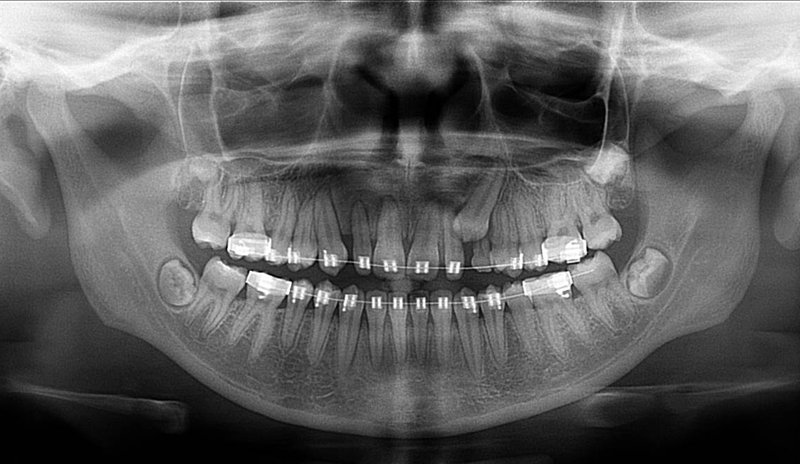

Jedná se o nejnovějším přístroj ze skupiny dentálních hybridních CBCT (3D) + 2D (pan i ceph) systémů. Přístroj umožňuje na základě jediného snímkování vytvořit všechny typy RTG zobrazení, které jsou pro lékaře potřebné.

Používaná technologii tzv. „kuželového paprsku“ a speciální senzory pro minimální zátěž při snímkování pacienta

(o více jak 80% nižší dávka proti klasickému CT).

Pomocí tohoto přístroje je možné zjisti skutečnou situaci v čelistních kostech pacienta tedy množství kosti - můžeme změřit skutečnou šířku i výšku kosti, i kvalitu kosti (hustotu) v místě uvažované implantace. 3D (tříprostorové) zobrazení umožňuje

zvýšit prostorovou představu operatéra ještě před vlastní operací a zároveň pacientovi lépe objasnit a ukázat oblast plánovaného zavedení implantátu.

Pacient „neumí číst“ RTG snímky, ale díky 3D zobrazení vidí „svoji skutečnou čelist“ – např. jak je nízká či úzká, vidí průběh nervu nebo velikost čelistní dutiny, což mu umožní i pochopení nutnosti v některých případech provést pomocné zákroky

ještě před vlastním zavedením implantátu (více - Augmentace - kostní štěp, sinus lift, kostní granulát...).

Pomocí počítačových programů – NewTom Implant Planning a coDiagnostiX si lékař sám provádí veškerá potřebná zobrazení a měření.

Vyšetření pomocí tohoto přístroje a získaná data používáme

pro každou implantaci, dále ve stomatochirurgii (zlomeniny čelistí, zuby moudrosti, cysty, onemocnění čelistního kloubu), ortodoncii (retinované zuby, nadpočetné zuby), parodontologii atd.